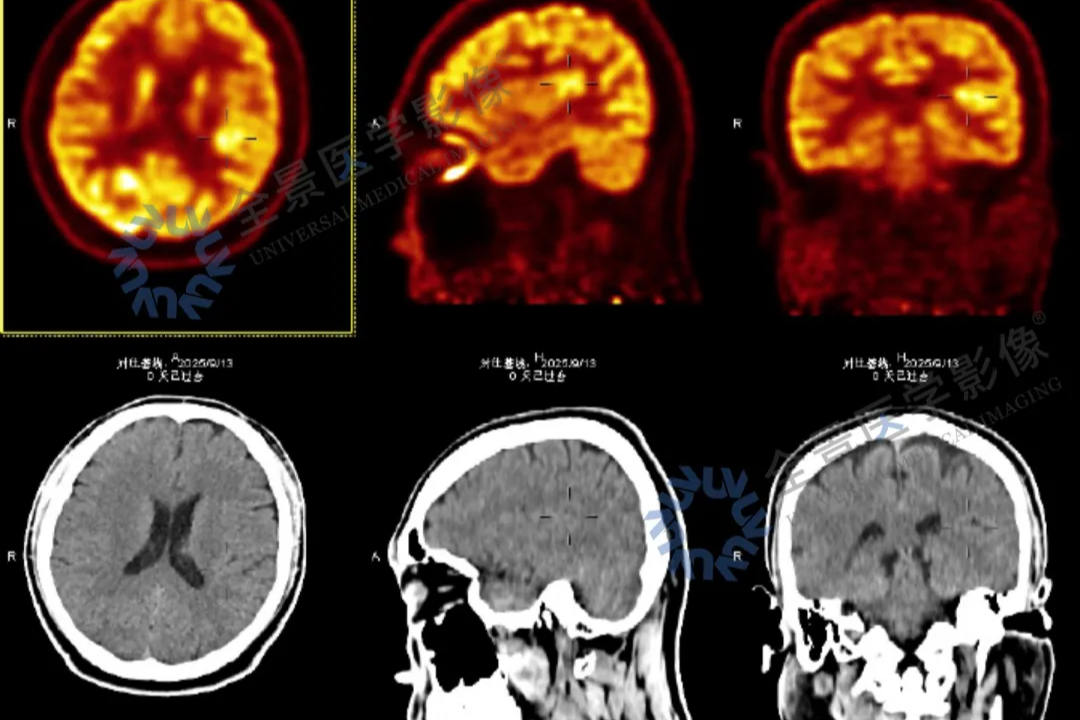

血脂血糖双高下的隐蔽风险:一次深度健检拉响「颅内炸弹」警报

2025-12-19